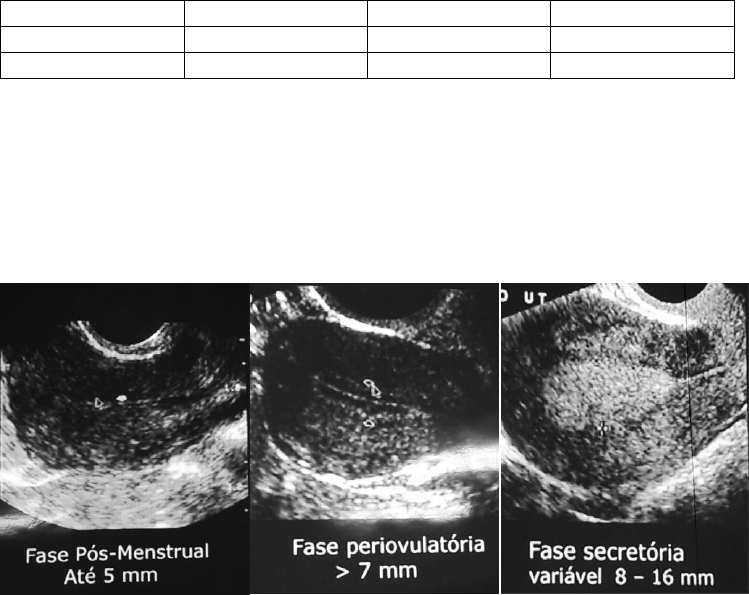

4. Endométrio

 Avaliar a espessura conforme o ciclo ovulatório e a ecotextura;

 Preocupação no climatério (período depois da última menstruação/pós

menopausa);

 Aumento da espessura sem terapia de reposição hormonal – hormônios

exógenos (TRH) pode indicar a ocorrência de câncer/neoplasias;

 Espessura: até 5mm sem TRH e até 10mm com TRH